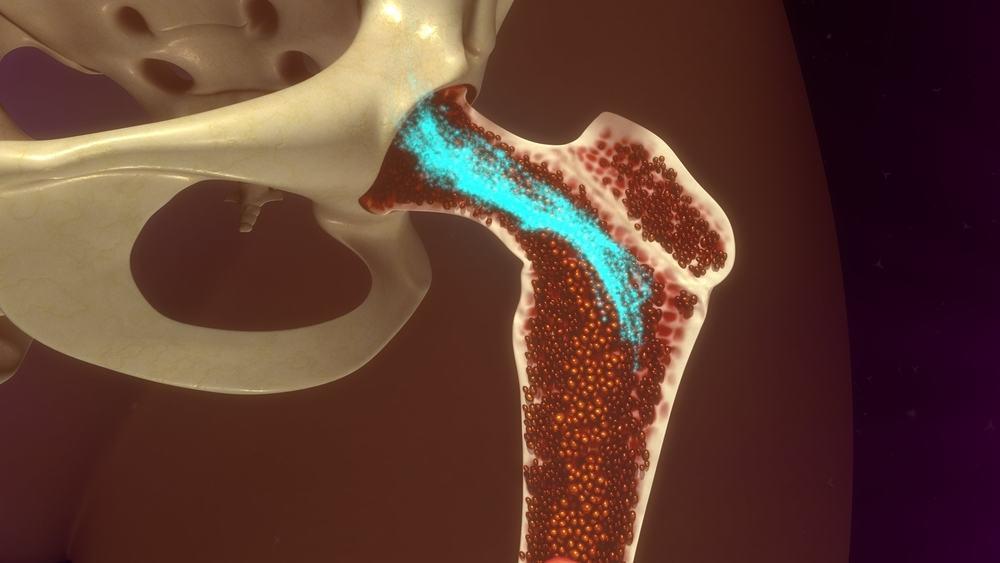

Ketika kalsium dalam darah rendah, hal ini disebut dengan hipokalsemia. Akibatnya, tulang jadi harus melepaskan kalsium miliknya demi mencoba menyeimbangkan kadar kalsium dalam darah. Sedangkan jika kalsium dalam darah tinggi (hiperkalsemia), kelebihan kalsium akan disimpan dalam tulang atau dikeluarkan dari tubuh melalui urine atau feses.

- Masalah tulang, seperti osteomalasia dan riketsia, di mana tulang menjadi lemah dan lunak karena asupan kalsium dan vitamin D tidak cukup. Hal ini membuat tubuh tidak bisa mengambil kalsium dari tulang untuk meningkatkan kadar kalsium dalam darah.